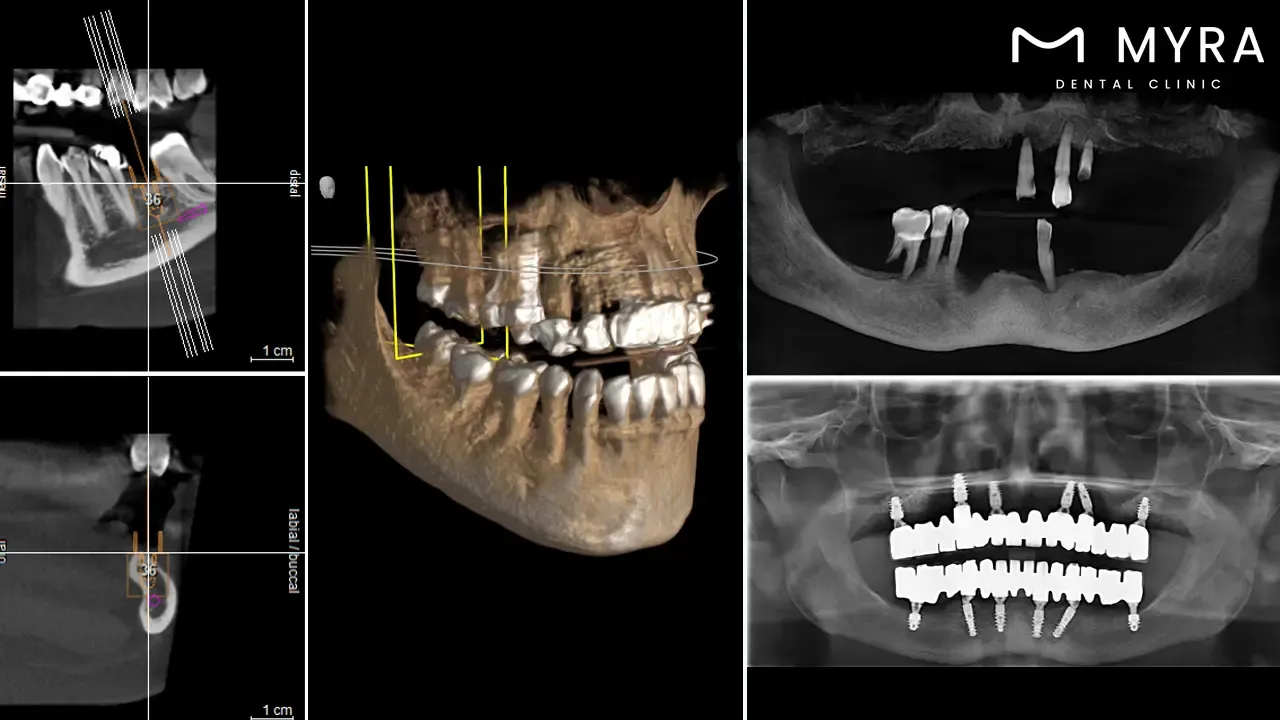

Evaluating the technologies that the clinic uses is essential. Advanced dental technologies, such as digital imaging, CAD/CAM systems, and laser dentistry, are widely used by respectable Turkish dental clinics.

Assessing the technology and standards of the clinic is crucial to assisting patients in making well-informed decisions regarding dental work in Turkey. The standard of care that patients receive is directly impacted by the calibre of the facilities and technology used by a dental clinic. Patients evaluating a clinic's standards have to consider elements, including order, cleanliness, and adherence to safety procedures. The clinic's dedication to the security and comfort of its patients is reflected in its clean, well-maintained surroundings.

The results of dental operations are greatly influenced by the technology employed. Modern methods and sophisticated technology improve the precision, comfort, and effectiveness of dental operations, which eventually improves patient outcomes. Patients obtain optimal oral health outcomes and anticipate a superior quality of service by selecting a clinic with cutting-edge technology and high standards. The result ensures that individuals getting dental work done in Turkey have a good experience and feel confident.

The technologies have a substantial impact on the precision, efficacy, and correctness of dental procedures. It enhances the patient experience by demonstrating the clinic's commitment to modern methods and understanding technical features. Dental care in Turkey meets or exceeds patients' expectations for quality and safety, as standards and technologies are aligned with their expectations. Turkish dentists are dedicated to giving their foreign patients the best dental care, as evidenced by their priority on clinic technology and standards.